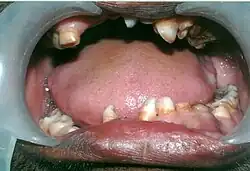

Mouth showing many over-retained deciduous teeth and some missing teeth.